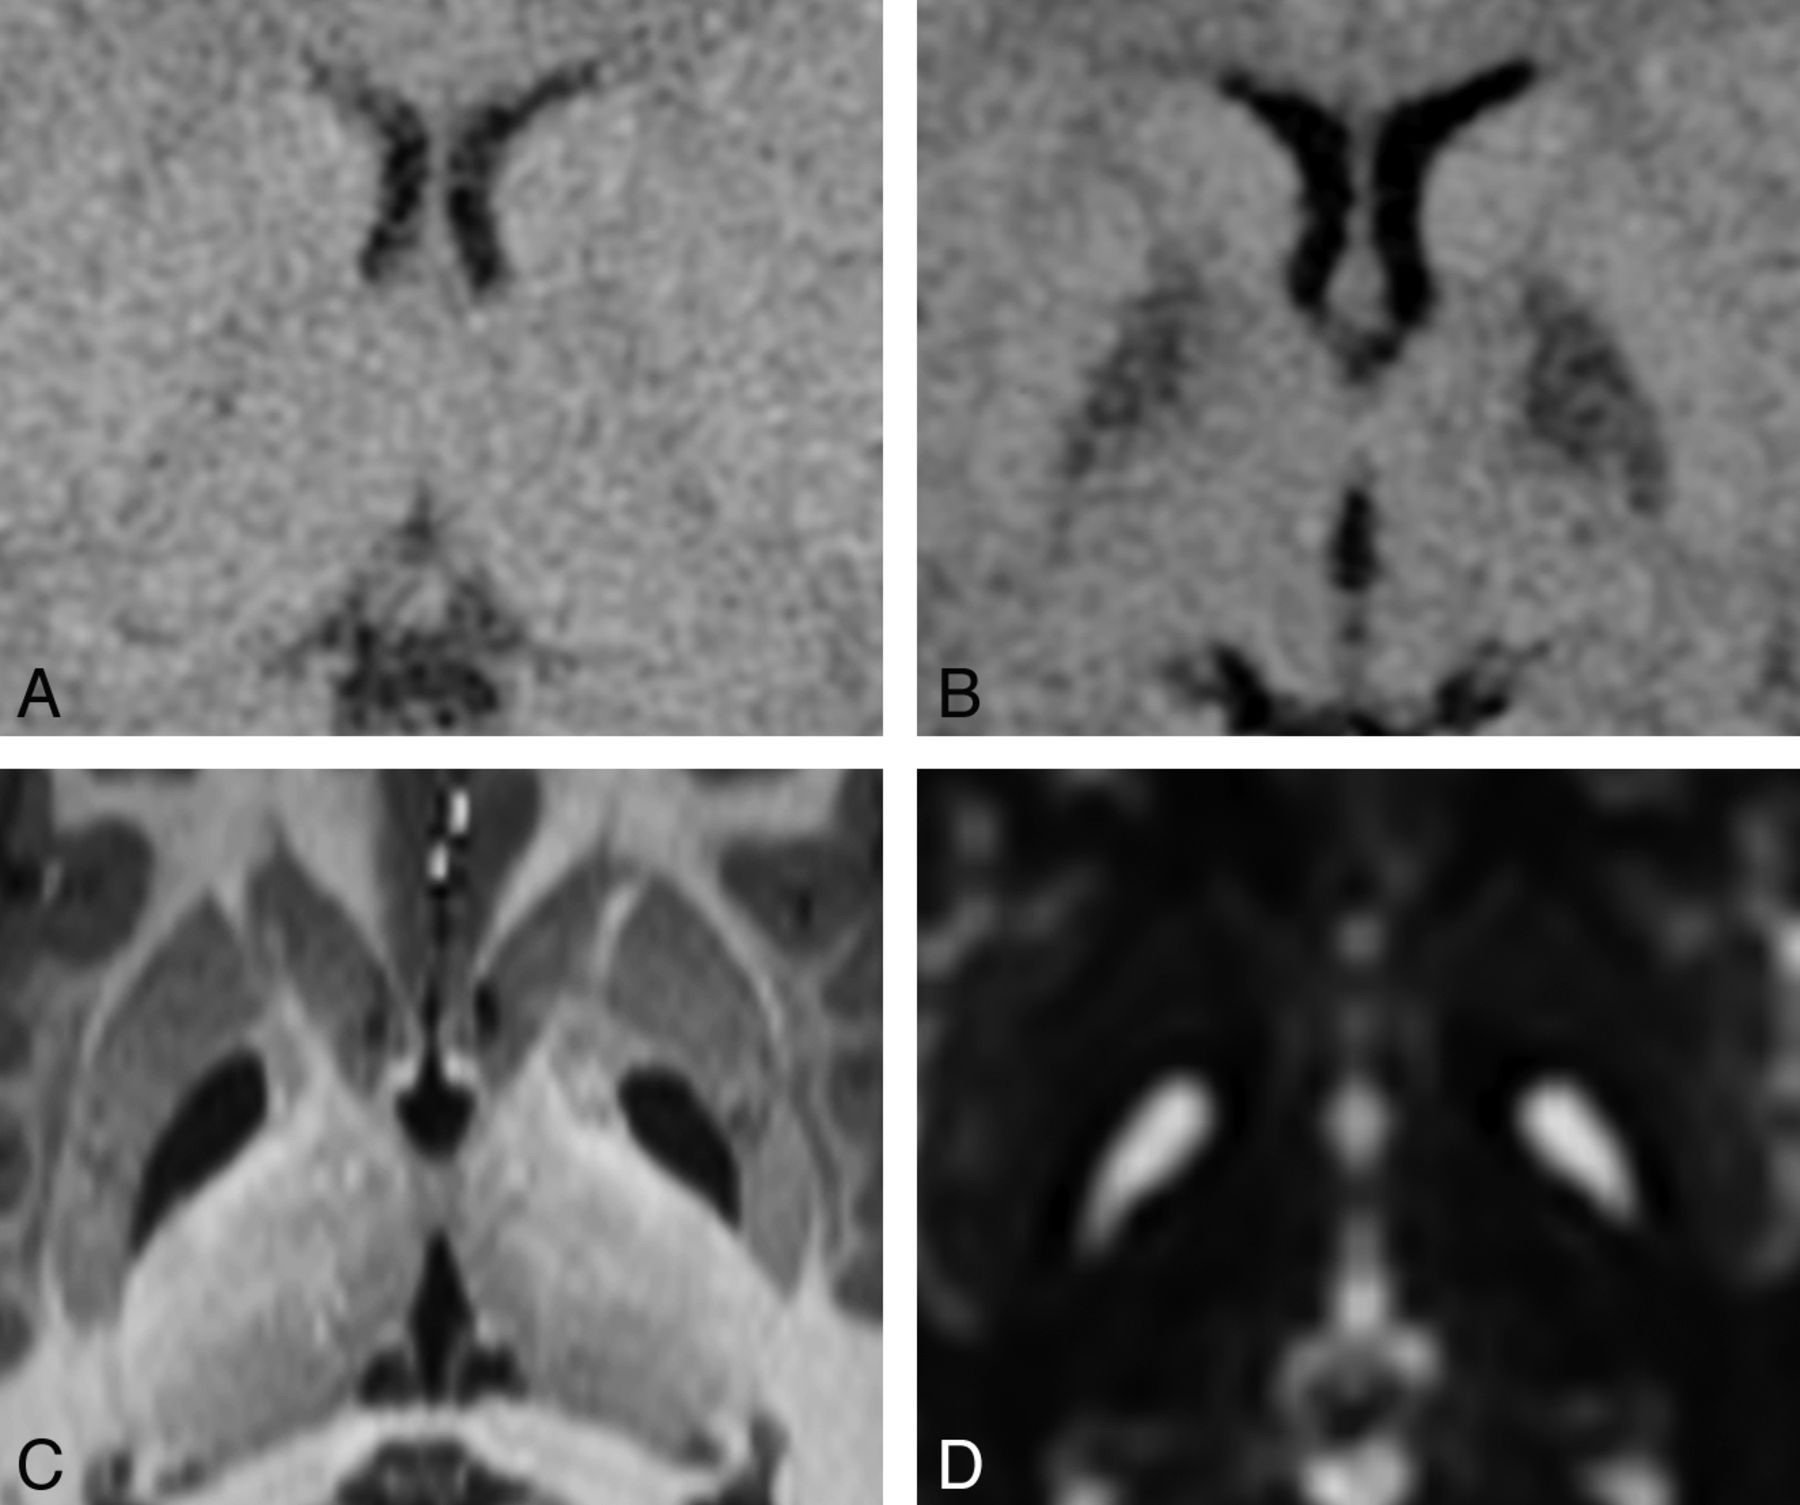

Distribution of SNr Infarcts

Lacunar infarcts of the SNr. Due to the small size of the cell clusters that form the SNr (near or below the lower limit of MR imaging resolution), detection of these infarcts can be difficult. A, Tiny bilateral infarcts of the SNr are seen on a bFFE image. The resolution of this image is 0.6 × 0.6 × 1.0 mm per voxel. The infarcts measure approximately 1 mm. Both are found in the anterior location. B, Slightly larger bilateral infarcts of the SNr are seen on an MPRAGE image with a resolution of 0.9 × 0.9 × 1.0 mm per voxel. These infarcts are in the middle location. C, Bilateral infarcts at 2 sites (anterior and posterior) in the SNr are seen on an MPRAGE image. SNr infarcts were found in only 3 distinct locations, which we are designating by their relative positions; the anterior location was the most common (20 infarcts), followed by the posterior location (9 infarcts). The middle location was the least common (5 infarcts).

Detection of SNr Infarcts

We observed a difference in sensitivity for the detection of SNr infarcts related to the type of imaging performed. Among patients for whom bFFE images were available, SNr infarcts were detected in 9 of 16 (56%). However, among patients who had only 3D-T1WI, SNr infarcts were detected in 8 of 22 (36%). No SNr infarcts were detected for the 2 patients scanned outside our institution without any 3D imaging sequences. When both types of images were available, no SNr infarcts were detected on the 3D-T1WI that were not also detected on the bFFE images. Availability of bFFE images was determined by the date of the examination, rather than by any patient-related factors because this sequence was added to our scan protocol partway through the study. We expect that had the bFFE images been obtained in all patients, more SNr infarcts would have been detected.